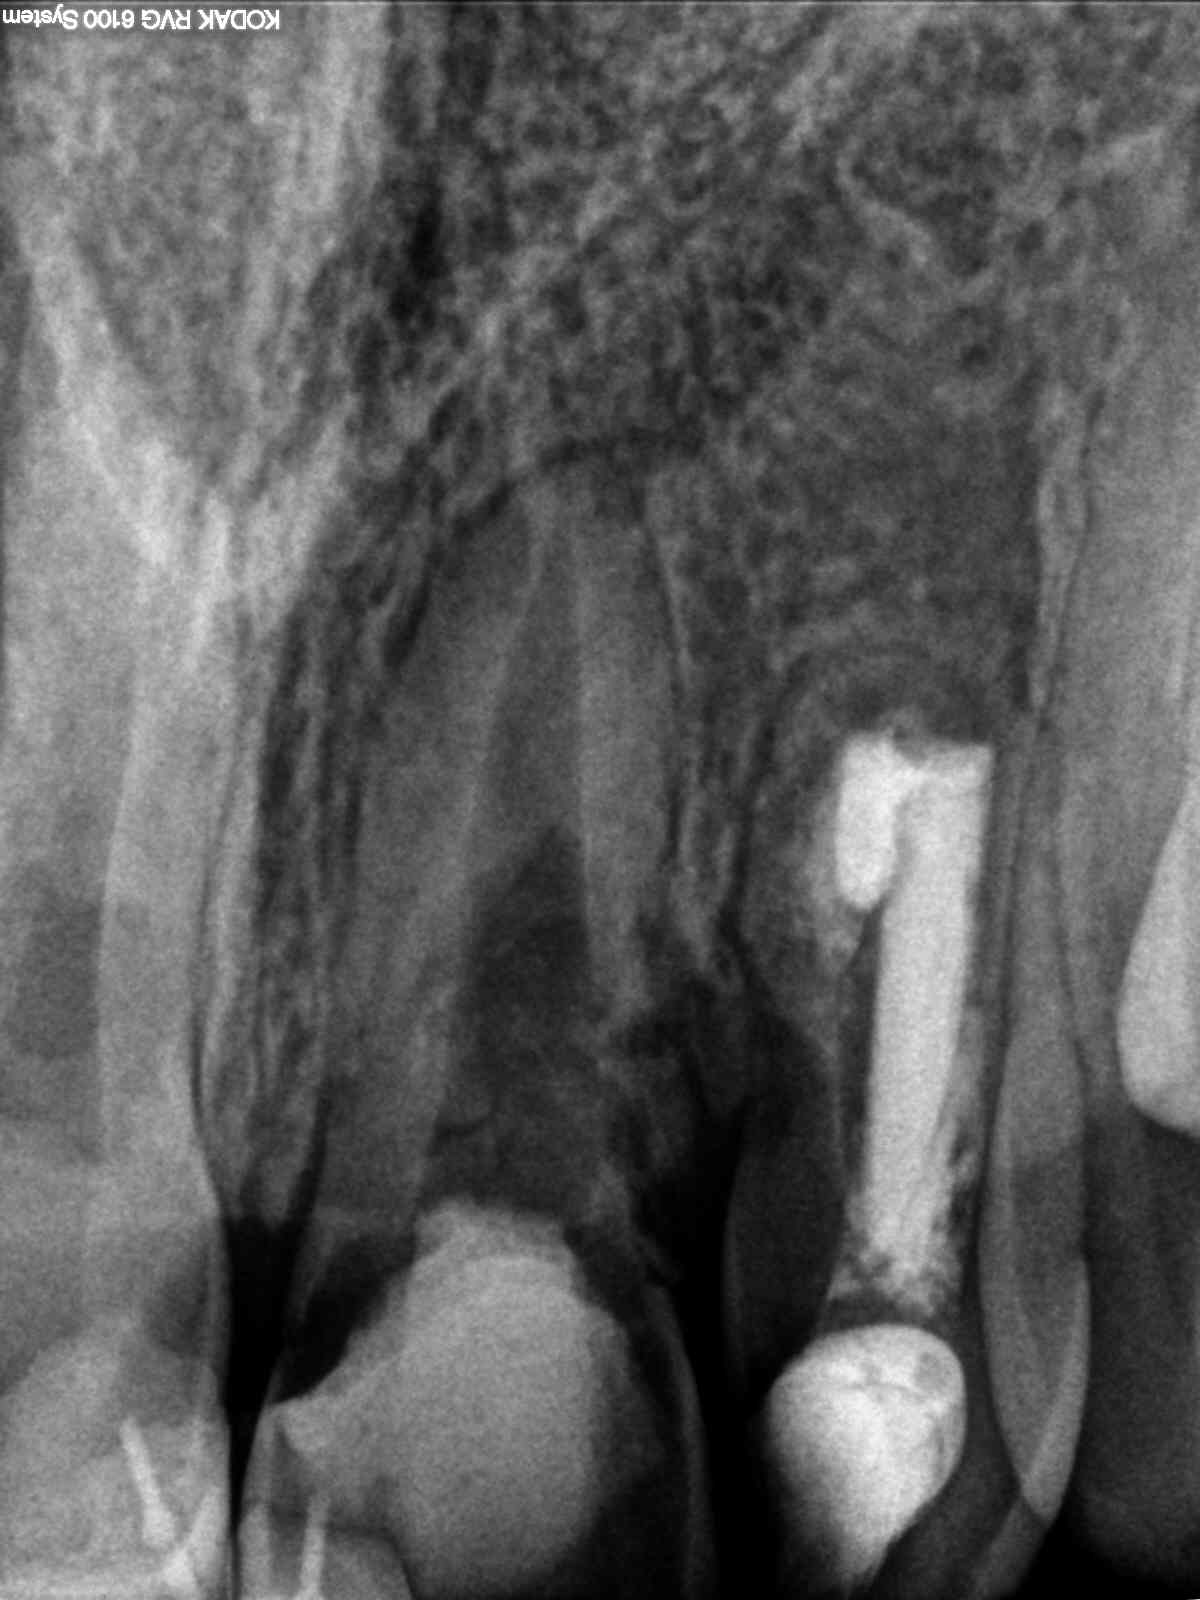

R2

Wer hätte es gedacht , …